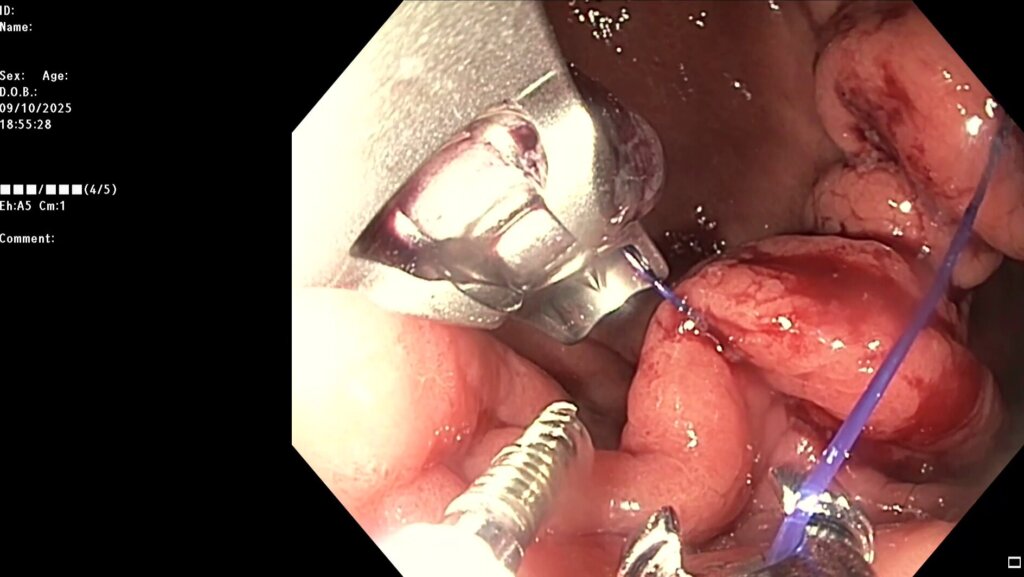

После предварительного обследования произведена операция: ESG + АПК (APC) свода; всего использовано 6 швов, время процедуры ≈ 120 минут.

Под видеоконтролем выполнена эндоскопическая рукавная гастропластика: сшивание стенок желудка при помощи аппарата Overstitch Boston Scientific по длине тела с целью уменьшения объёмов съедаемой пищи.